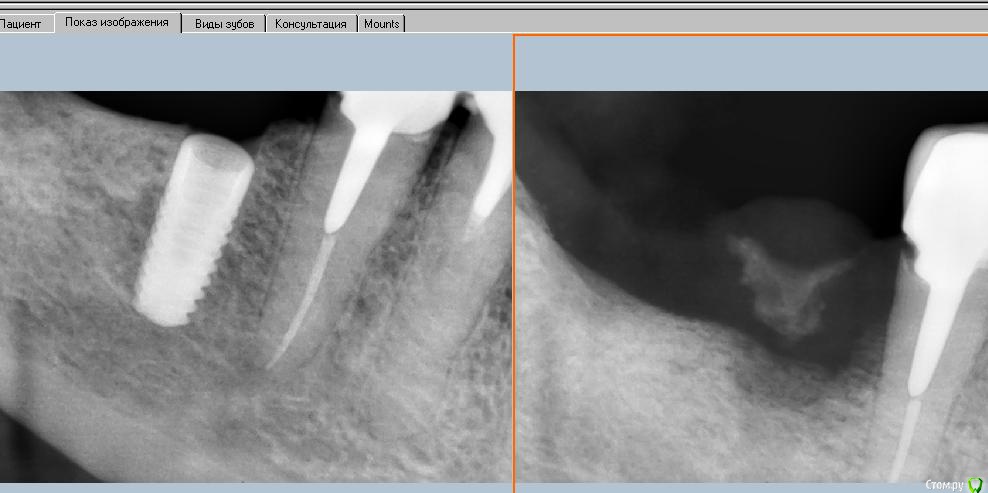

kriokov Опубликовано 23 марта, 2016 Поделиться Опубликовано 23 марта, 2016 А как на рентгене можно определить ожег ли это? Как кость должна убывать? через месяц так примерно, ожог кортикальной , секвестрация, болт удален через 7 суток после установки, секвестр через 1 месяц. В ранние сроки по снимку не определишься ожог это или еще что. 3 Ссылка на комментарий